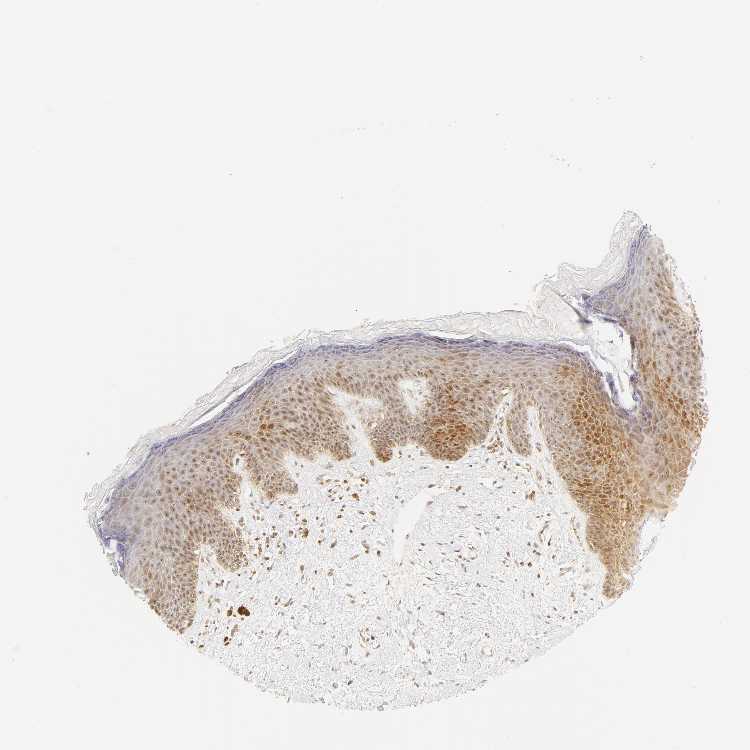

SKIN 2 - Antibody stainingi

Antibody staining in the annotated cell types in the current human tissue is reported as not detected, low, medium, or high, based on conventional immunohistochemistry profiling in selected tissues. This score is based on the combination of the staining intensity and fraction of stained cells.

Each image is clickable and will lead to virtual microscopy that enables deeper exploration of all samples and also displays staining intensity scores, fraction scores and subcellular localization as well as patient and tissue information for each sample.

Antibody HPA004716

Epidermal cells High